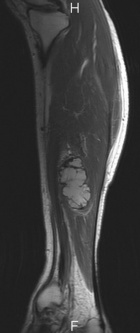

42 year old male presents with c/o L leg/calf pain that is worse with activity for the past year.